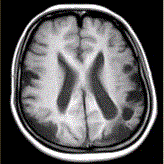

问题 女性,22岁。癫痫发作及智力异常。MRI显示见下图。 关于该病描述正确的是

选项 A.脑萎缩 B.双侧顶枕叶软化灶 C.蛛网膜囊肿 D.双侧顶枕叶脑梗死 E.脑积水 F.脑炎

答案 AB

解析 AB